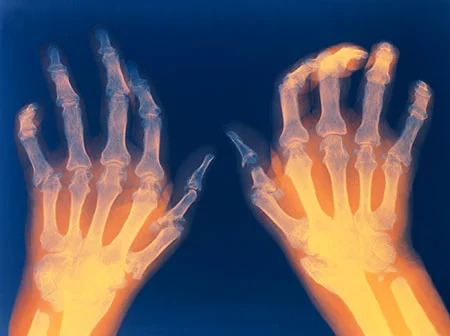

- Rheumatoid Arthritis (RA): Rheumatoid arthritis is one of the most well-known forms of inflammatory arthritis. It primarily affects the synovium, which is the lining of the membranes that surround the joints. This leads to joint inflammation, pain, and, if left untreated, joint deformities. RA can also affect other parts of the body, such as the heart, lungs, and blood vessels.

- Inflammatory Arthritis: Inflammatory arthritis is marked by joint inflammation, leading to symptoms such as joint pain, swelling, and stiffness. The inflammation can cause joint damage and deformities over time.

While fibromyalgia is categorized as a condition related to arthritis, it is not a typical form of arthritis because it lacks the characteristic tissue inflammation and does not result in joint or muscle damage. Nonetheless, some categorize it as a rheumatic condition due to its ability to cause pain and tenderness in the joints and surrounding tissues. Typically, individuals with fibromyalgia exhibit normal X-ray and blood test results, which can be frustrating as family and friends may mistakenly assume they are in good health. In contrast, individuals with arthritis often display abnormal test results and may exhibit visible signs of pain, such as swollen or deformed joints.

- Imaging Studies: X-rays, ultrasounds, or magnetic resonance imaging (MRI) may be used to visualize the joints and assess for joint damage and inflammation.